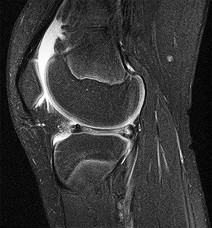

Question 4:

A 22-year-old female soccer player undergoes primary anterior cruciate ligament (ACL) reconstruction using a bone-patellar tendon-bone autograft. Postoperatively, she experiences loss of terminal extension and anterior knee pain. An MRI indicates graft impingement against the intercondylar roof. Which of the following technical errors during tunnel preparation is the most common cause of this specific impingement pattern?

Correct Answer: Tibial tunnel placed too anteriorly

Explanation:

Placing the tibial tunnel too anteriorly is the most common cause of intercondylar roof impingement. The tibial tunnel should be placed posterior to the intersection of Blumensaat's line and the tibial plateau when the knee is in full extension. If placed anterior to this line, the graft will impinge on the notch roof during terminal extension, leading to a loss of extension and potential graft failure.